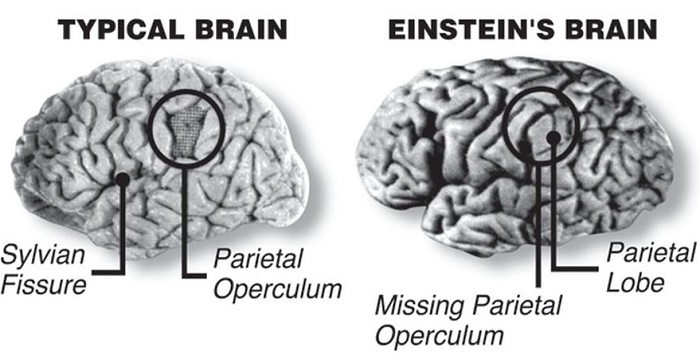

Https www alamy com a specimen of nobel physicist albert einsteins brain is seen in a glass slide at an exhibition at the wellcome collection in london march 27 2012 weve pickled it dessicated it drilled it mummified it chopped it and sliced it over centuries yet as the most complex entity in the known universe the human brain remains a mysterious fascination with samples of albert einsteins preserved brain on slides and specimens from other famous and infamous heads such as the english mathematician charles babbage and notorious mass murderer william burke an exhibition opening in london this week image377121679 html (Dateityp jpg)

Einsteins Brain High Resolution Stock Photography And Images Alamy